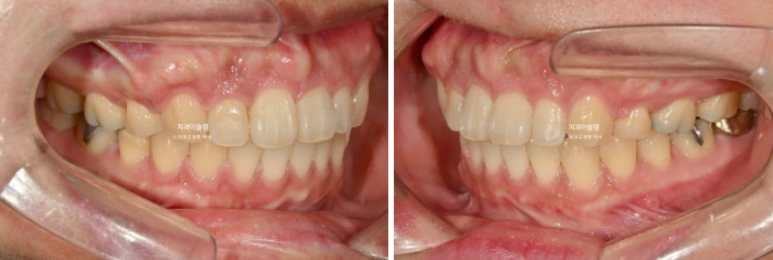

Let’s compare the before and after.

The total treatment period was 3 years. If the patient had visited once a month, it would likely have taken about 2 years and 3 months.

With active intrusion of the front teeth, the amount of gum exposure improved after treatment.

The smile line harmonizes well with the lower lip.

After treatment, the angulation of the front teeth is good.

The upper front teeth were intruded by 2 mm. Thanks to that, gum exposure when smiling decreased, and the gummy smile was resolved.

The front teeth moved back a great deal, but the key point is that they did not become over-inclined inward.